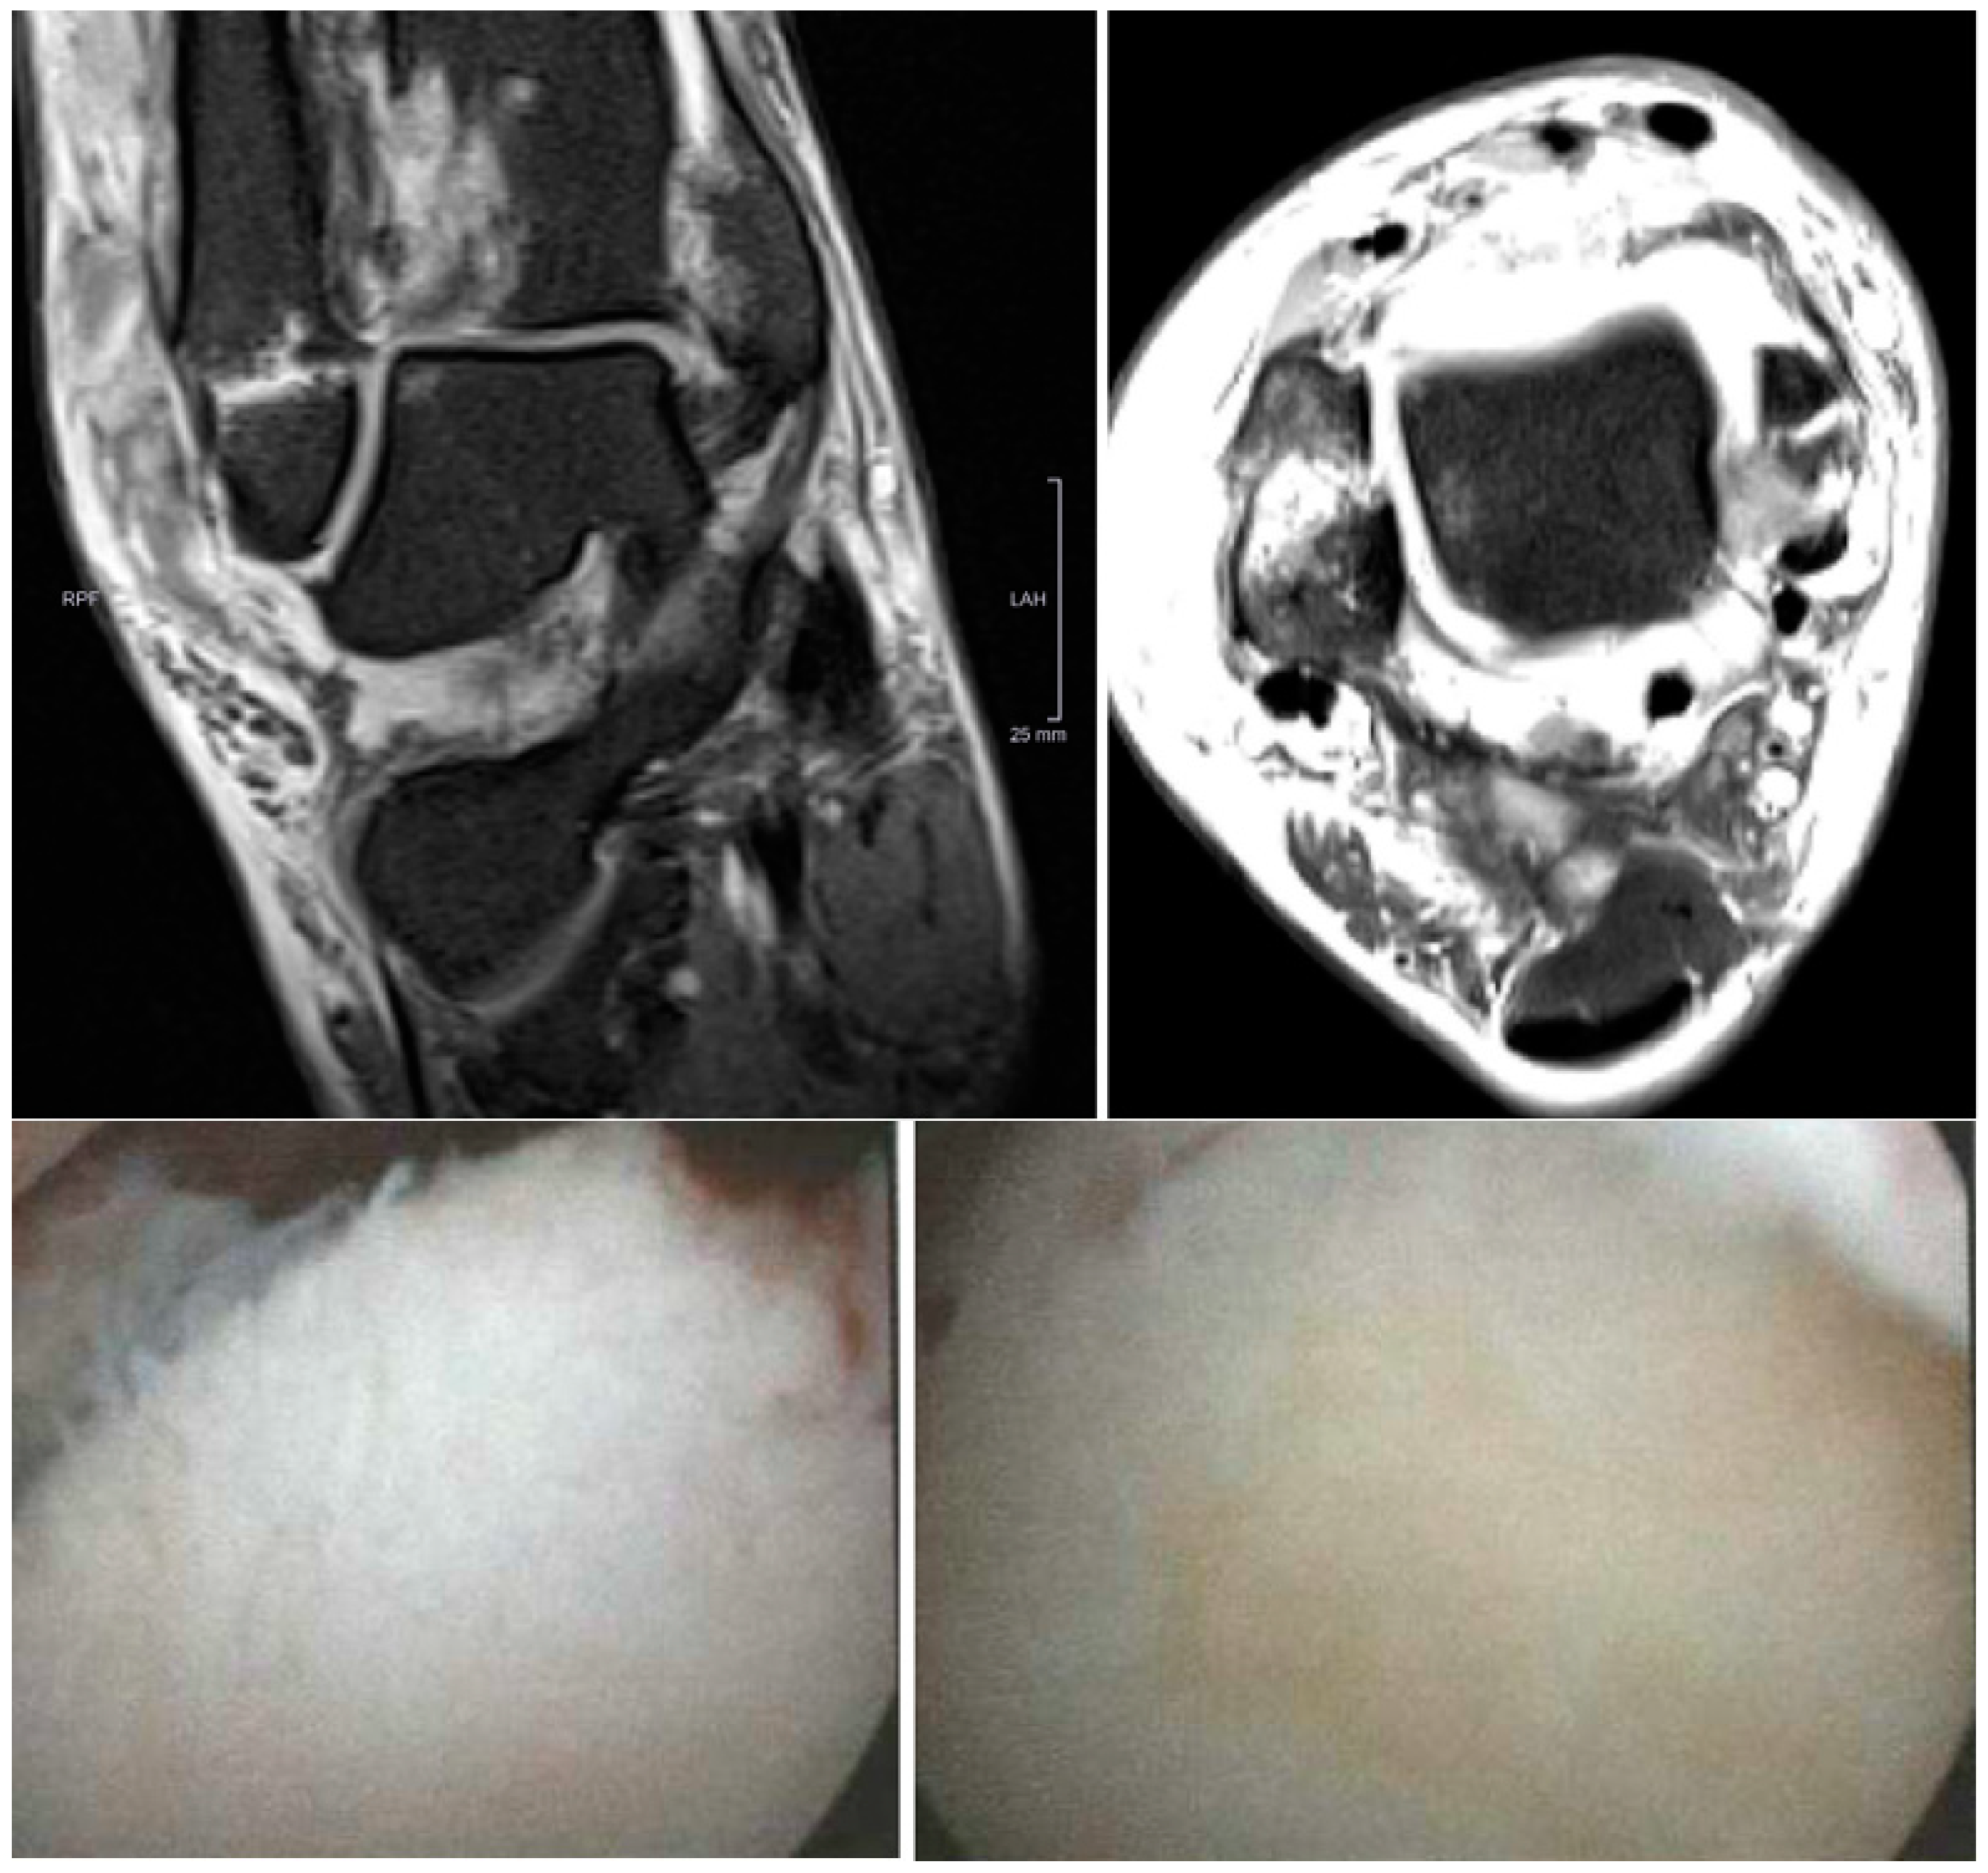

2.2. Radiological Assessment

2.3. Arthroscopic Evaluation

3.1. Assessment of the Preoperative MRI Scans

3.2. Evaluation of the Intraoperative Arthroscopic Findings